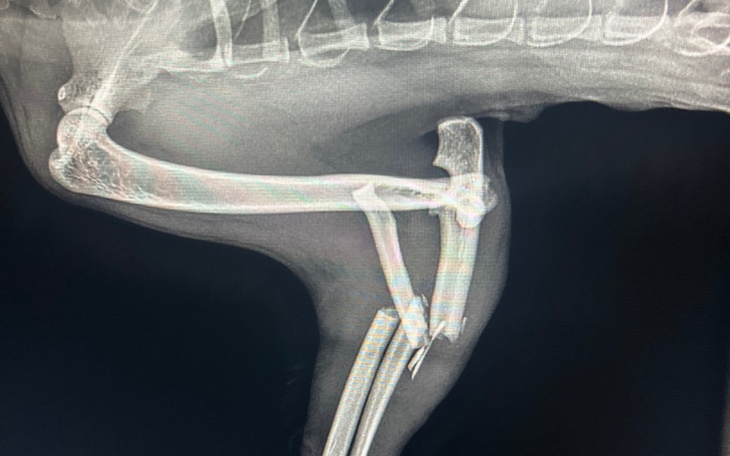

Chcielibyśmy się z Wami podzielić pilną potrzebą ratowania życia pięknej kocięcej duszy, która jest teraz w naszym ciepłym domu. Nasza ukochana Jadzia, uliczna kotka, padła ofiarą tragicznego ataku rottweilera. Jej przednia lewa łapka jest złamana w kilku miejscach i pilnie potrzebuje operacji.

Jadzia to młoda kotka, pełna energii i radości. Wkrótce stanie się częścią naszej rodziny, a jej życie zmieni się na lepsze. Jednak teraz musimy walczyć, by uratować jej przednią łapkę. Dobra wiadomość jest taka, że mamy wspaniałego weterynarza, który jest gotów przeprowadzić operację. Jednak koszty operacji wynoszą 2000 złotych, a musimy działać niezwłocznie, w tym tygodniu, aby uratować jej nóżkę.